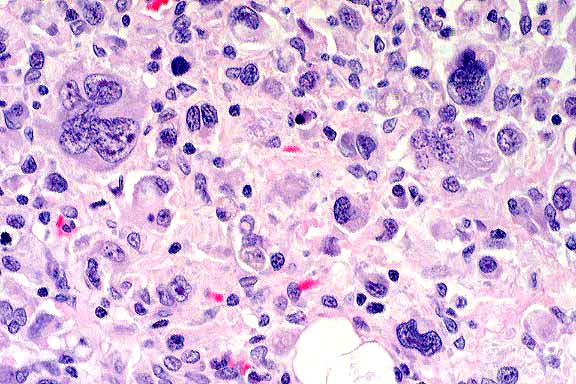

- Case 11-1. Spinal cord. Neoplastic cells have pleomorphic

nuclei, anisocytosis, and mitotic figures.

- Conference Note: A poorly differentiated neoplasm

effaces portions of the brain stem and infiltrates the meninges

and subpial parenchyma. The neoplasm is composed of highly pleomorphic

round cells. Neoplastic cells multifocally occur within Virchow-Robins

space in less affected areas of the brainstem, and there are

perivascular inflammatory infiltrates both within the tumor and

less affected areas of neuropil. Neoplastic cells are characterized

by variably-distinct cell borders with abundant, eosinophilic

cytoplasm which is occasionally vacuolated or contains phagocytized

cells or debris. There is marked variation in nuclear size and

shape.